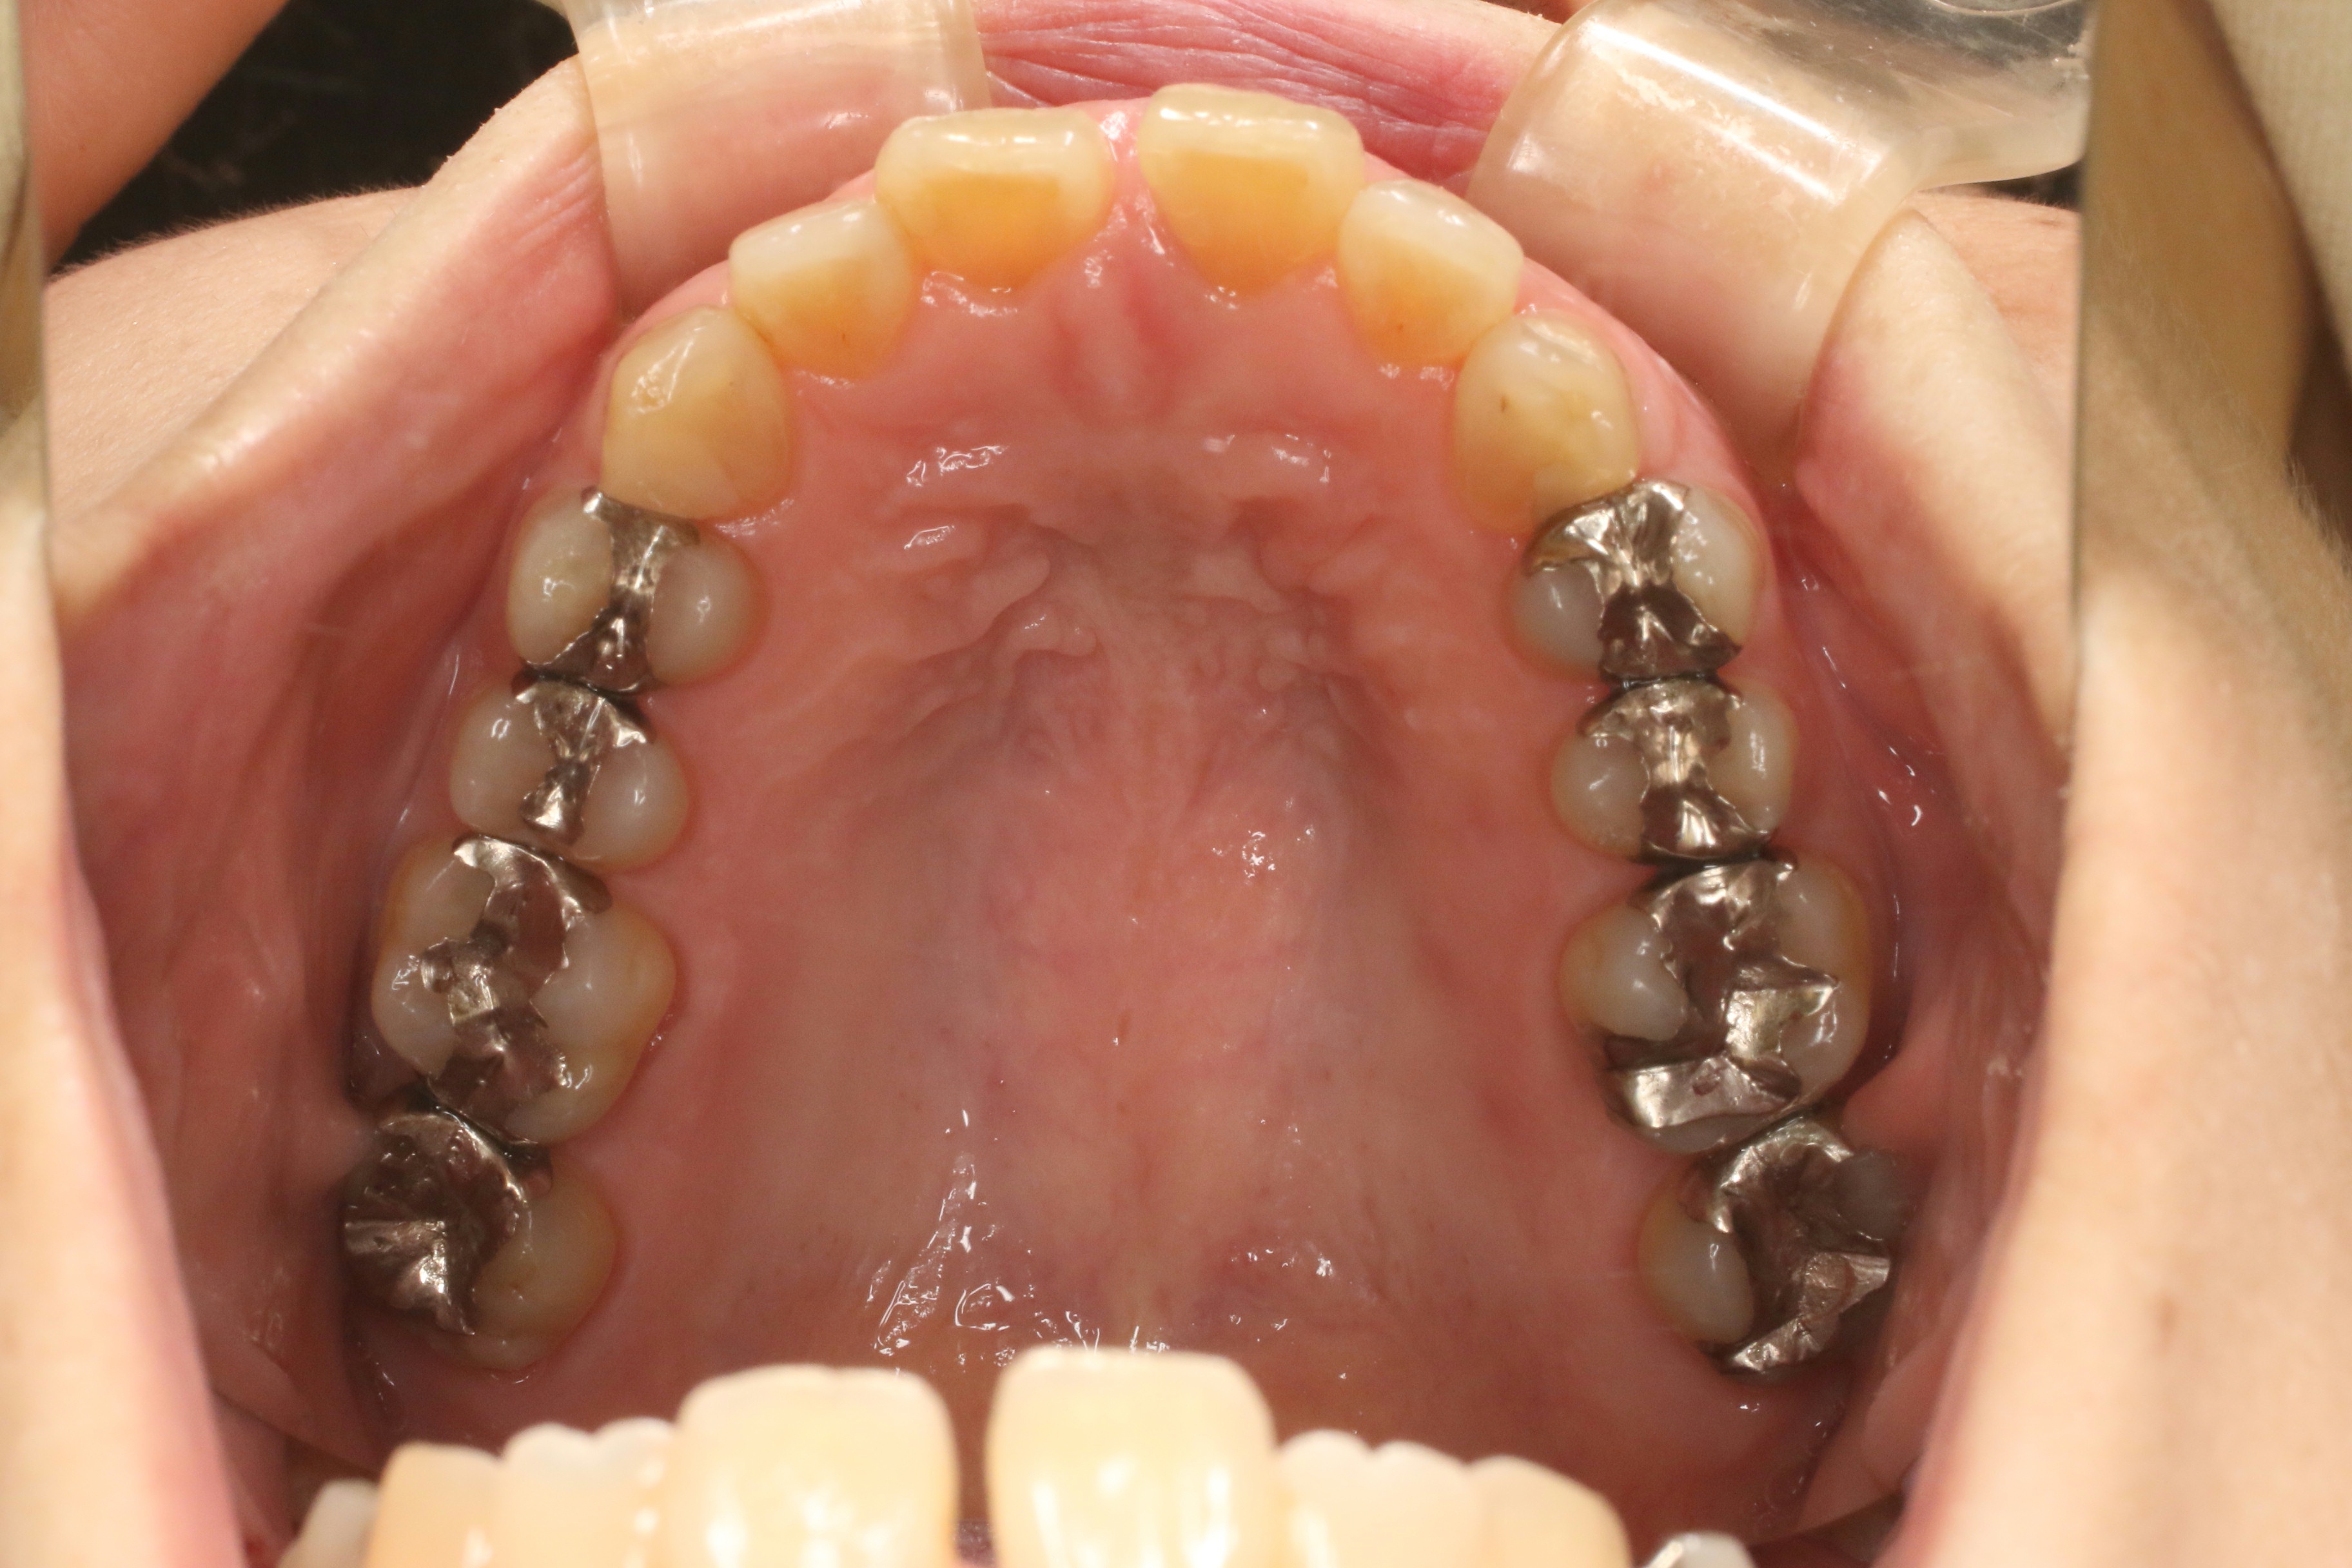

すきっぱ(治療期間:1年/通院回数12回)

年齢層

50代

性別

女性

主訴

すきっぱ

治療費用

1,177,000円

治療期間

1年

抜歯

非抜歯

矯正の装置

ラビアル

副作用、リスク

・知覚過敏・痛み・発音障害・体質により金属アレルギーの発症・歯肉退縮・歯根吸収・ブラックトライアングル(歯と歯の間の根元にできる隙間)・歯磨きが上手く出来ない場合、むし歯や歯周病が進行・保定が不十分の場合、後戻りの可能性

Before

After